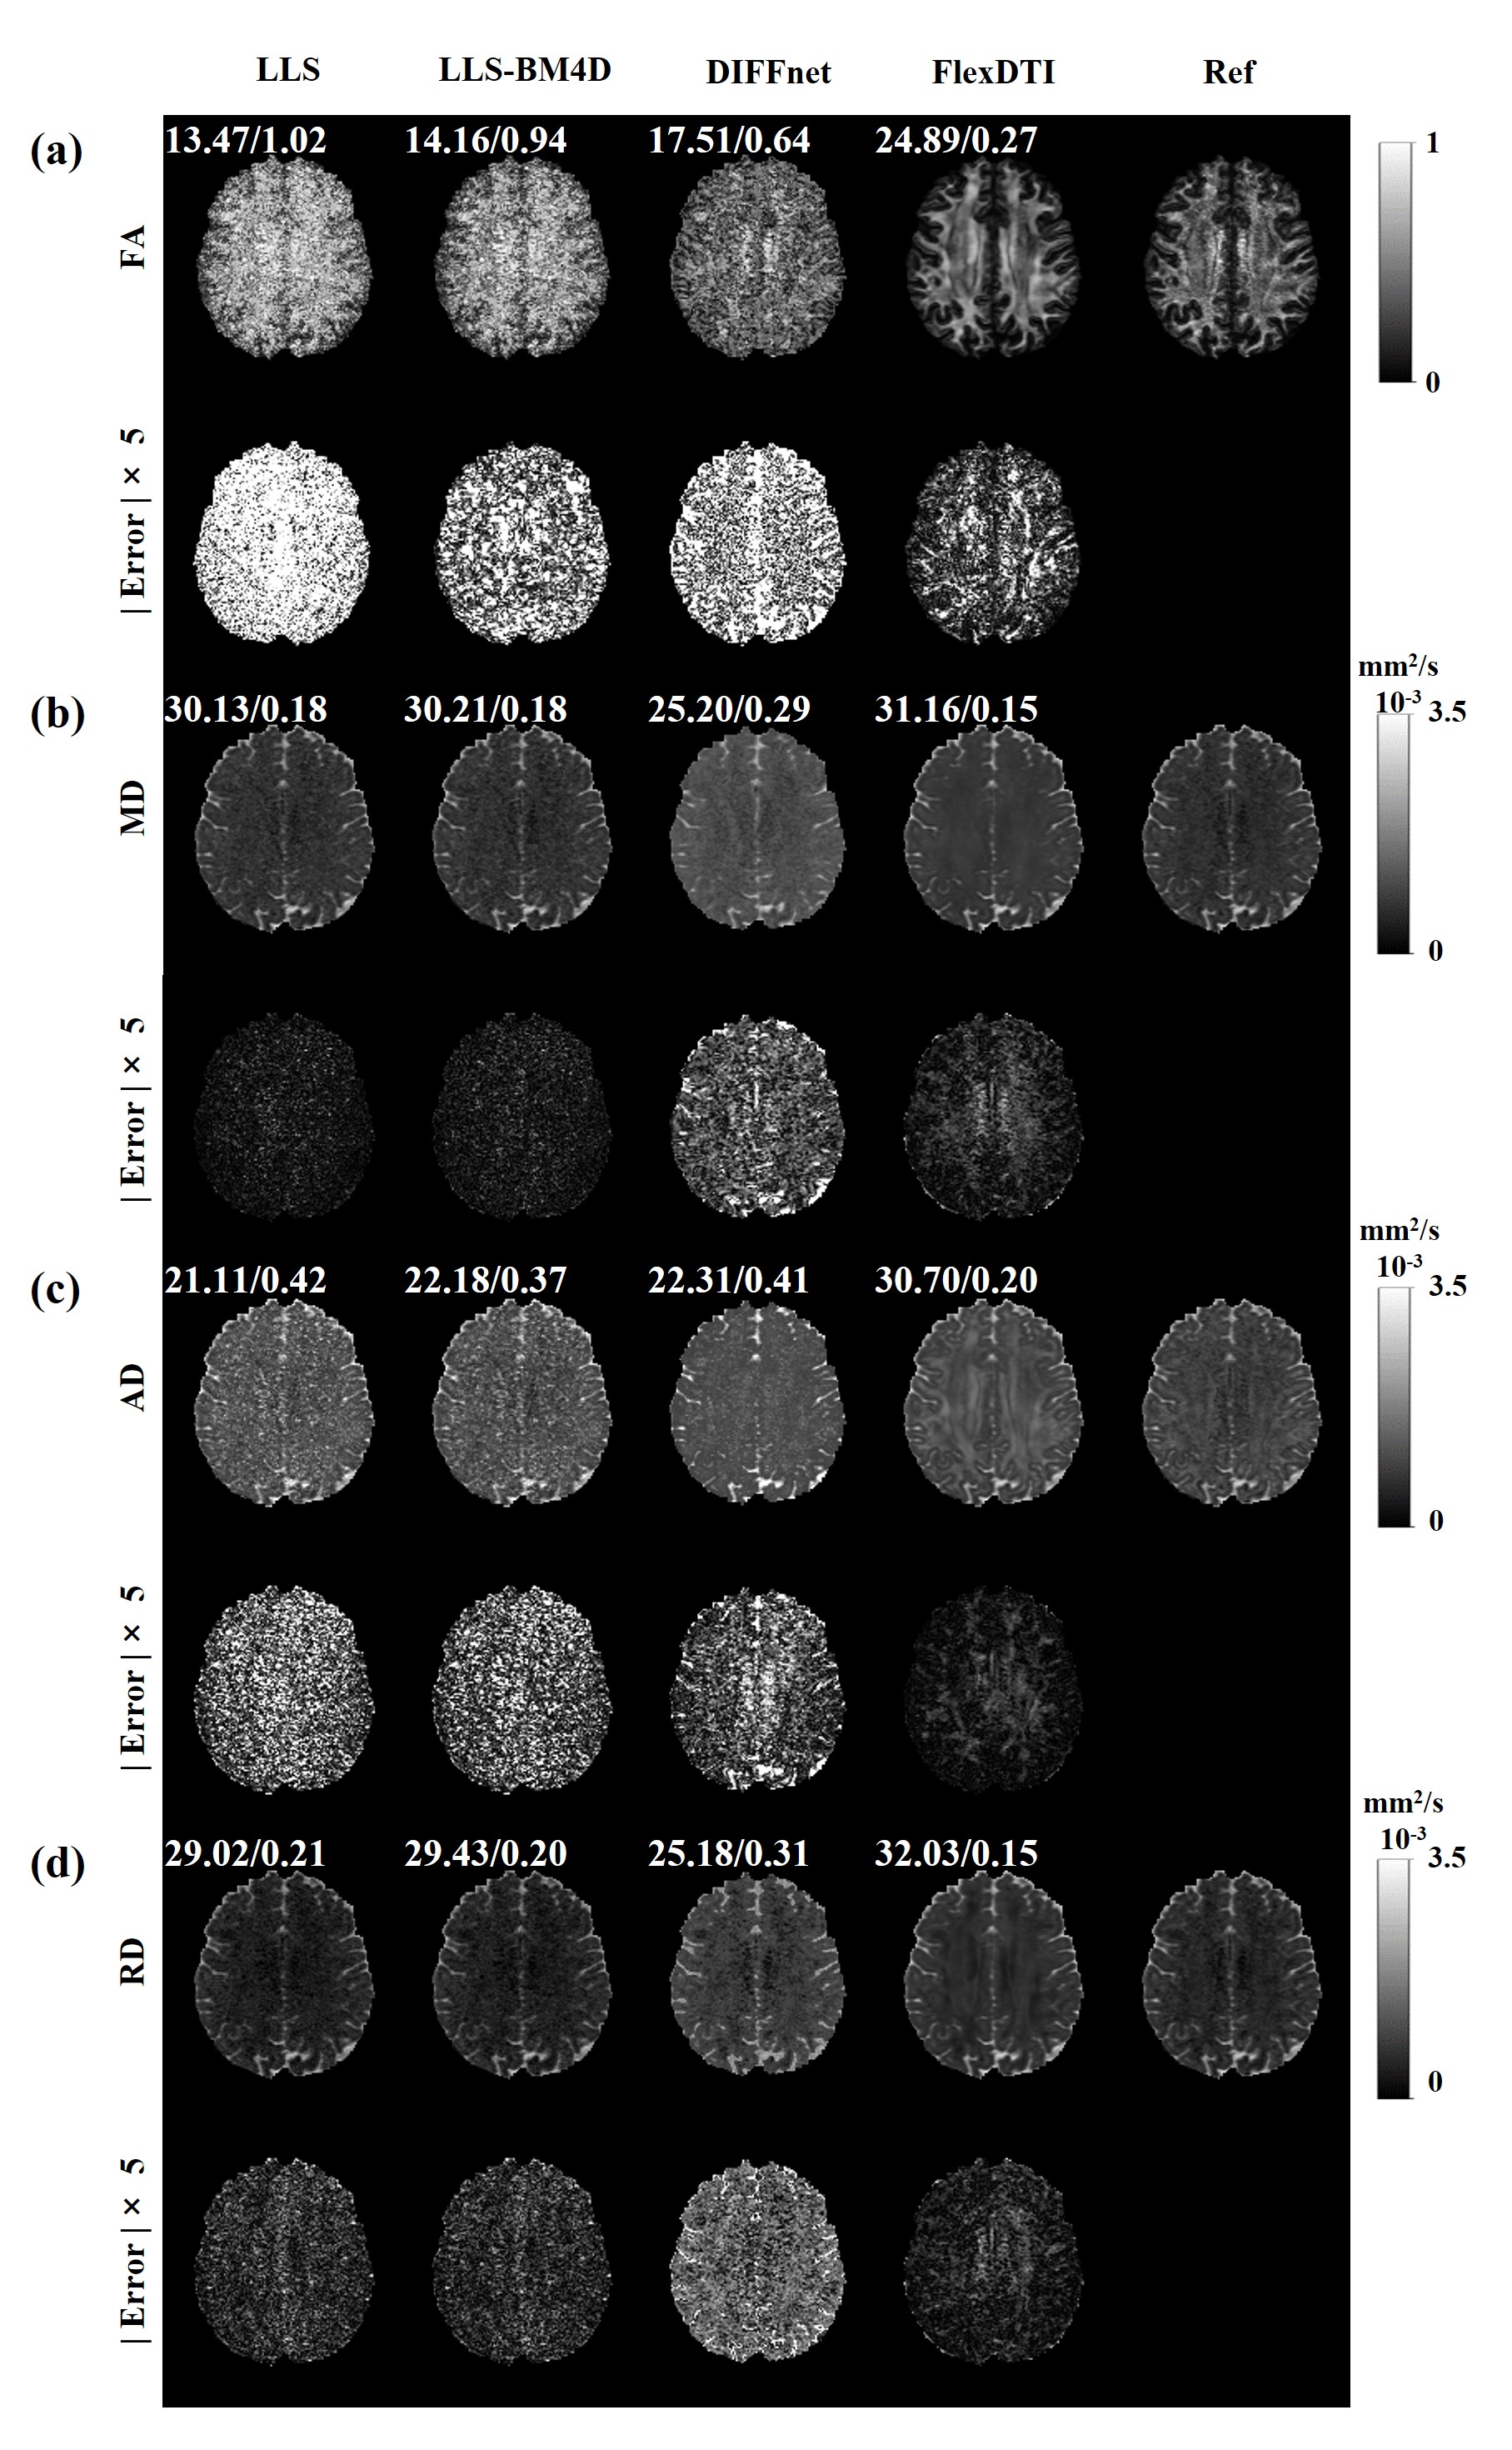

The DTI reconstruction of local clinical data (Figure 5) shows that our method is suitable for different scanners, indicating its strong generalization ability. Once the network is trained, it can be used for different diffusion gradient schemes on different types of scanners, which is of great convenience for the clinical application of deep learning-based DTI. It should be pointed out that, for high-resolution DTI, mitigating local volume effects enables finer structural resolution, holding significant implications for enhancing the accuracy of DTI in clinical applications (Wu et al 2013, Liu et al 2009). However, due to its prolonged scanning time, current clinical practice often utilizes lower resolution. On a clinical MRI scanner, a more common resolution is a 2×2×2 mm3𝑚superscript𝑚3mm^{3}italic_m italic_m start_POSTSUPERSCRIPT 3 end_POSTSUPERSCRIPT acquisition. Figure 8 shows the results of further evaluations of our method on typical clinical brain MRI protocols with three healthy volunteers. Figure 9 shows the performance of FlexDTI in other scan parameters like slice thickness, TE, phase partial Fourier and parallel imaging. According to the quantitative assessment of FA, MD, AD and RD, it can be seen that the proposed method still outperforms other methods for the typical clinical brain MRI protocols and keeps stability under different scan parameters, proving that the proposed model has good generalization performance.

Figure 8: Four parametric maps (FA, MD, AD and RD) reconstructed by LLS, LLS-BM4D, DIFFnet and FlexDTI using 6 DW images with flexible diffusion gradient directions for typical 2×2×2 mm3𝑚superscript𝑚3mm^{3}italic_m italic_m start_POSTSUPERSCRIPT 3 end_POSTSUPERSCRIPT acquisition. The references were reconstructed by LLS using 96 DW images. The PSNRs and NRMSEs are given at the upper left corner of each reconstructed image.